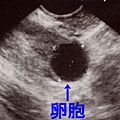

卵泡超音波